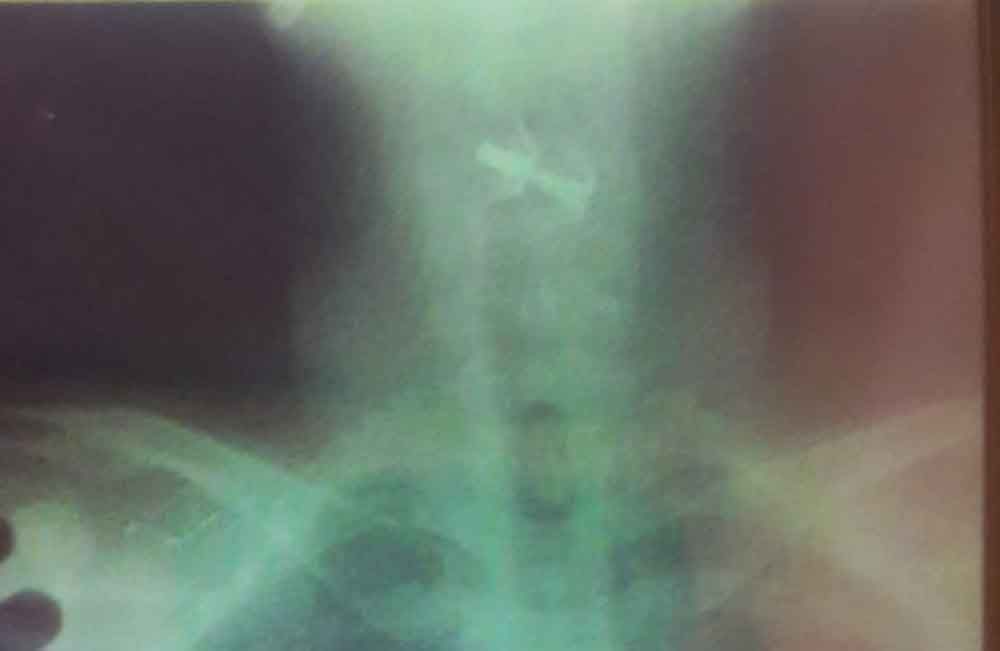

Supiyanto, warga Dusun Sampangan RT 03 RW 06, Desa Kedungrejo, Kecamatan Muncar, Banyuwangi ini dirawat intensif di RSU dr Soetomo Surabaya dengan kail yang tertancap di tenggorokan.

Menurut keterangan kakak korban, Siti Maesaroh, Supiyanto setelah menelan kail pancing tersebut mengalami muntah darah.

Diduga, luka yang dialami Supiyanto dinilai parah, sehingga harus di rujuk ke RSU dr Soetomo Surabaya, Jumat (9/8) sekitar pukul 19.30 Wib untuk dilakukan operasi.

"Korban pernah dirawat di RS Licin, 3 kali korban. Dan sebelumnya korban juga pernah menelan Baut, uang logam, dan plastik kresek," katanya.